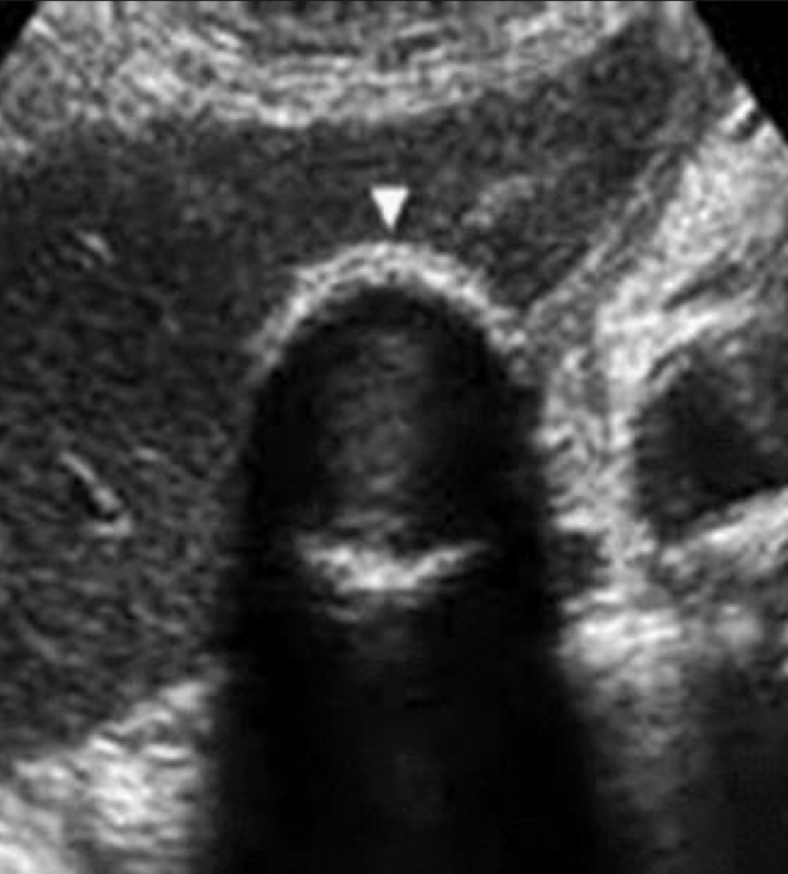

gangrenous cholecystitis

necrotic GB due to prolonged infection

s/s: painful

SONO: thickened irregular edematous wall; pericholecystic abscess; perforations; echogenic densities that fill the lumen of the GB that has:

no shadow

not gravity dependent

no layering effect due to increased viscosity of the bile

??